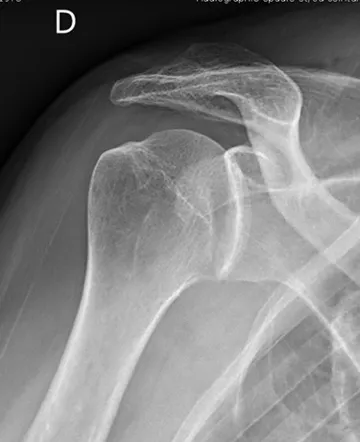

QUELS SONT LES EXAMENS COMPLÉMENTAIRES À RÉALISER ?

Dans un premier temps des radiographies permettent d'avoir une orientation diagnostique en corrélation avec l'examen clinique du chirurgien. Il s’agit du bilan de débrouillage qui sera complété le plus souvent par un arthro-scanner ou une IRM.

- La luxation aigue d’épaule : c’est le « déboitement de l’épaule » : Elle survient dans un contexte le plus souvent traumatique entraînant une douleur brutale de l’épaule (+/- un craquement). Le patient consulte alors en urgence. Le diagnostic suspecté par l’examen clinique et confirmé par une radiographie. Le traitement consiste à remettre en place la tête de l’humérus. On parle de réduction de la luxation. Cette manoeuvre peut être faite sous simples calmants ou lors d’une courte anesthésie générale. Le patient est ensuite immobilisé dans une attelle coude au corps pour une durée de 2 à 6 semaines. Après ce délai, la rééducation est débutée. Lors de cet épisode aigu, il n’y a pas lieu de réaliser d’intervention chirurgicale en urgence sauf dans certains cas très particuliers.